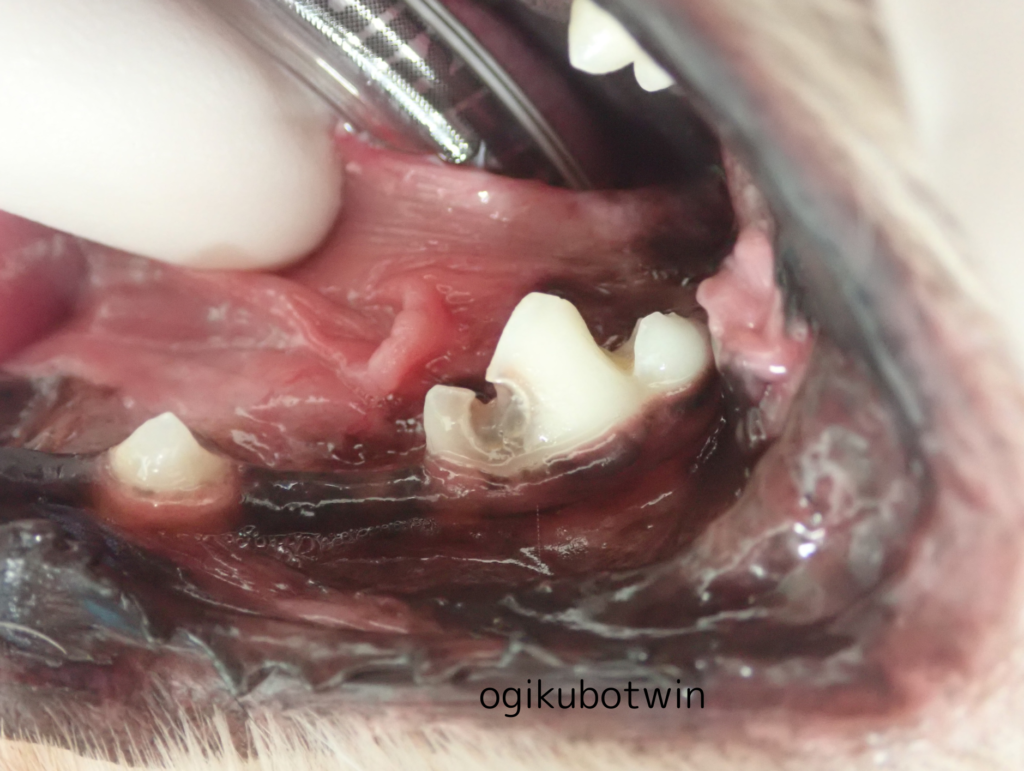

診察時に左下顎第一後臼歯(奥歯)に裂溝が見られました。

※裂溝…臼歯(奥歯)の咬合面、頬側面、舌側面等に見られる溝のこと

この歯は虫歯(う蝕)になっているため飼い主様と相談した結果、今後のリスクを回避したいとのことで抜歯することになりました。

全身麻酔下にて歯科レントゲンを撮影し虫歯になっている歯を抜歯しました。

レントゲンでも歯に大きく穴が開いていることがわかります。